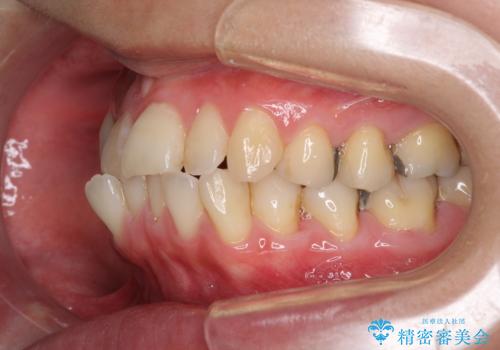

- 前歯のデコボコを気にして来院された患者様です。

上下前歯の先端同士が接触する切端咬合であったため、上顎は歯列を拡大し、下顎はIPR(歯と歯の間を削る)により叢生を解消しながら歯列を小さくすることとしました。

矯正装置にはインビザラインを用いることとしました。

治療途中に前歯に歯髄充血を思わせる痛みが認められたため、無理のない歯の移動と頻繁な経過観察を行いました。

切端咬合はスムーズに解消され、前歯の負担を軽減させることができました。